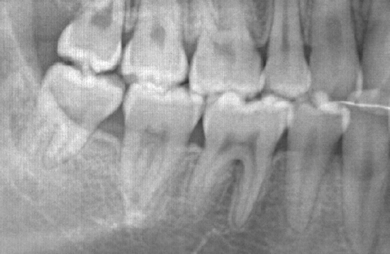

| 治療方針 | 歯のがたつきが大きいことより上下左右第一小臼歯を抜歯して、マルチブラケット装置にて治療。また、親不知がまっすぐ生えることができず横を向いている状態なので、まっすぐにする隙間があることから親不知も使用し、矯正を行う。 | ||||||||||||||||||||||||||||||||